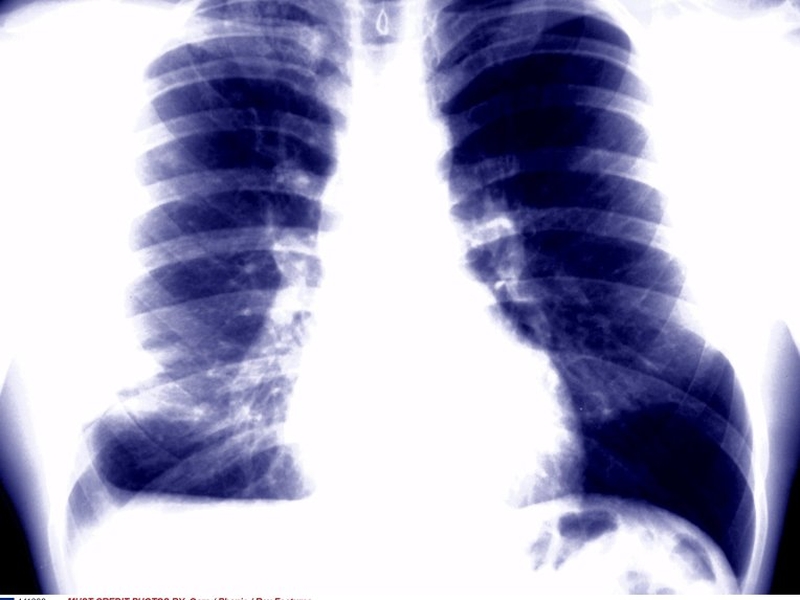

Ireland has a shortage of consultant radiologists, with just over half the European average.

It said the clinical demand for radiology services is increasing steadily here and these factors have led to high workloads for Irish radiologists, when compared with their peers in other countries.

The faculty said that X-rays and scans from smaller hospitals, which are harder to staff, could then be reported by radiologists based in larger centres within the hospital group, to ensure complete cover and provide easy access to expert second opinions.